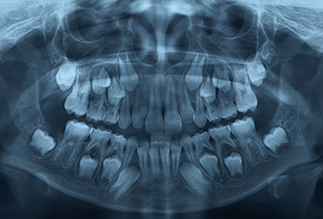

EXTRAORALS

These are bigger X-rays which shows the entire dental arch/ dentition / both the jaws etc. Gives the clinician an overall information regarding the dental health status and condition of an existing problem/disease of a particular patient,